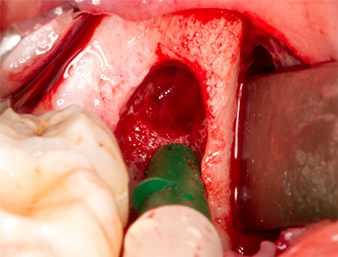

After block and local anaesthesia, the operating site was opened up and the soft tissue exposed for buccal retromolar access (Fig. 3).

To obtain autogenous material for subsequent wound treatment, healthy bone chips were harvested from the surroundings of the root remnant with a piezo surgical instrument (Piezomed B5) (Fig. 5).

The autogenous tissue was removed with the scraper-shaped section of the working part of the instrument and stored in a physiological saline solution until further use (cf. Fig. 13).